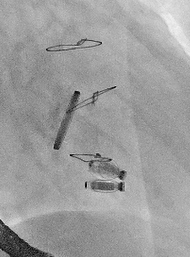

手术在经食道超声心动图和DSA引导下进行,武汉协和医院董念国教授团队使用NeoBlazar™经导管三尖瓣夹合器,经股静脉穿刺,送入导丝建立右心房通路,送入三尖瓣夹合器械,在右心房调整双层控弯导管,将第一枚夹合器置于三尖瓣前叶与隔叶间反流最大区域,在DSA与超声双重指引下跨瓣进行瓣叶的捕获与夹合,在经食道超声心动图反复确认手术效果后,释放三尖瓣瓣膜夹;第二枚夹合器顺利送至后隔交界,捕捉三尖瓣后叶和隔叶,确认瓣叶夹持稳固后释放夹合器。此次术中共植入2枚瓣膜夹,瓣膜夹位置和功能良好,术后即刻超声心动图评估三尖瓣反流降至轻度,手术取得圆满成功。

术中DSA图

术后DSA图